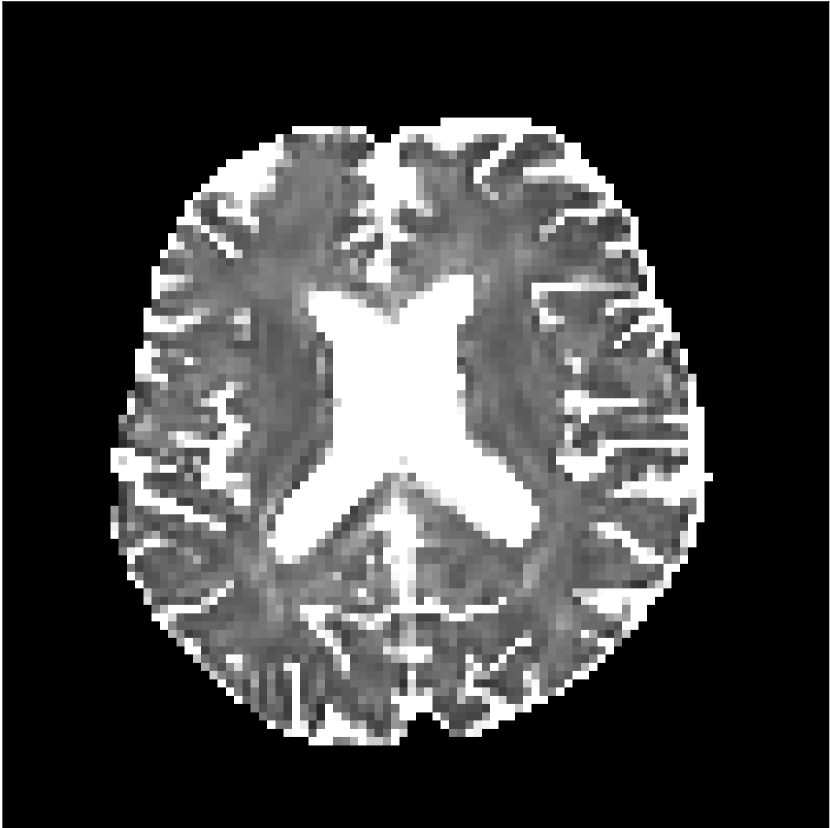

Figure 10 compares mean diffusivity maps across various partial Fourier factors between the CCNN and state-of-the-art methods.

No PF

7/8 PF

6/8 PF

5/8 PF

SoA

MD, μ𝜇\mum2/ms

CCNN

Figure 10: Comparison of mean diffusivity (MD) parameter maps across PF factors of 5/8ths, 6/8ths, 7/8ths, and without PF (No PF). The methods include state-of-the-art (SoA) and CCNN methods. Without partial Fourier, both methods are similar; however, as the PF factor increases, substantial artifacts are introduced in the SoA method, particularly around the lateral ventricles. The CCNN method is able to reduce the introduction of artifacts.

The methods perform similarly without partial Fourier acceleration, but as partial Fourier acceleration increases, the image is continually degraded in the SoA method, with "black voxels" appearing around the lateral ventricles. The CCNN method mitigates the appearance of these artifacts in the parameter maps.